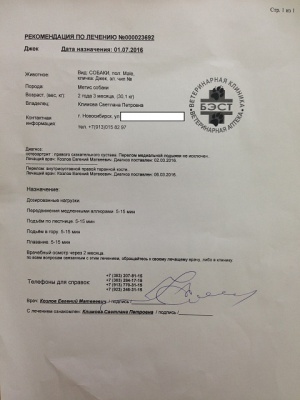

Последний раз были на приеме у Козлова Е.М. 01.07.2016.

Евгений Матвеевич не только произвел осмотр, но и внимательно посмотрел на Джека в движении, на улице, при ходьбе по лестнице. Следующий плановый осмотр через два месяца. Два месяца реабилитации и обучения жизни на четырех лапах.

Евгений Матвеевич не только произвел осмотр, но и внимательно посмотрел на Джека в движении, на улице, при ходьбе по лестнице. Следующий плановый осмотр через два месяца. Два месяца реабилитации и обучения жизни на четырех лапах.

– оплата приема хирург Козлов Евгений Матвеевич, клиника Бэст (чек, товарный чек 1, лист приема – документ 1) – 520 руб.;

– оплата приема хирург Козлов Евгений Матвеевич, клиника Бэст (чек, товарный чек 1, лист приема – документ 1) – 520 руб.;